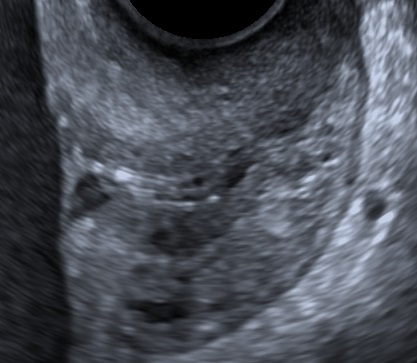

- Median sagittal view of the cervix.

- Calipers between the triangular area of echodensity at the external os and the V-shaped notch at the internal os.